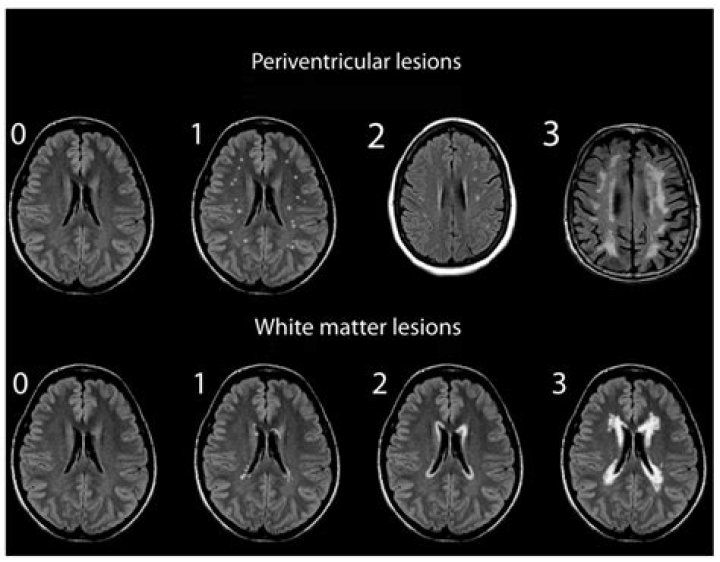

Multiple studies have found that people with migraines have an increased risk of brain lesions. The two main types of lesions found in migraineurs include: White matter hyperintensities (WMH): These lesions appear bright white on certain sequences of MRI scans.

Studies show that having migraines can make you more likely to get brain lesions. These painful headaches are linked to two main types of lesions: White matter lesions.

What are migraine spots on MRI?

What does migraine look like on an MRI? In some people with migraine, MRI scans of the brain may show white spots or areas. These are caused by lesions or irregular areas in the white matter of the brain. White matter tissue is deep in the brain and is mostly made up of nerves.